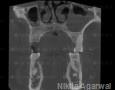

CBCT :

Yes